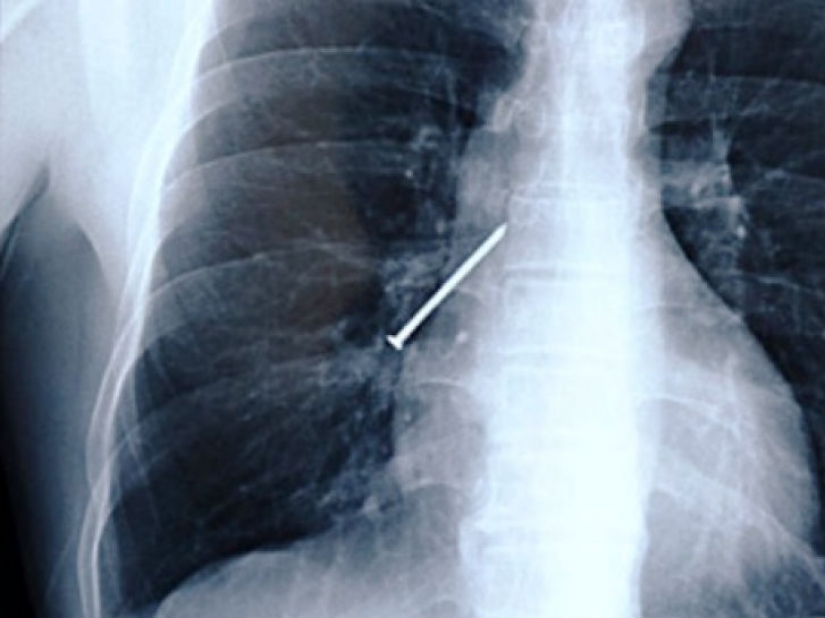

¿Alguna vez has ocupado en sus dientes un clavo cuando sus manos están ocupadas con un martillo? He aquí a los hombres de China, que durante la operación de la tos.